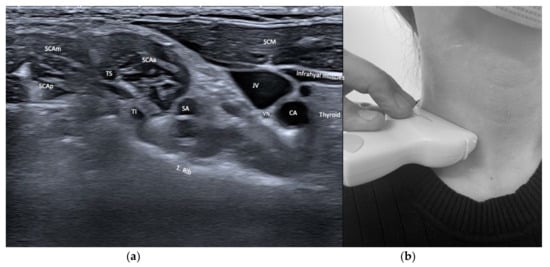

| Sternocleido-mastoid (SCM) | Contraversion of head and neck Ipsitilt of head and neck Anteflexion of head and neck with bilateral activation | + | ++ | Infrahyoid/supra-hyoid muscles, omohyoid, carotid artery, jugular vein | Dysphagia (particularly if injected bilaterally) |

| Scalenus anterior (SCAa) | Anteflexion of neck | +++ | +++ | Thyroid, carotid artery, brachial plexus, phrenic nerve, lung | |

| Scalenus medius/posterior (SCAmp) | Ipsitilt of neck | ++ | ++ | Brachial plexus, lung | |